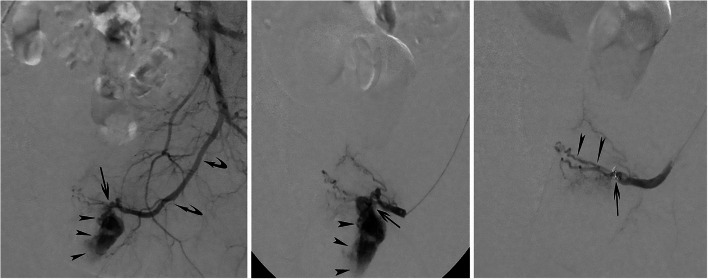

Case presentation: Two patients with a iatrogenic and non-iatrogenic urethral bleeding respectively are presented. Conservative management, including Foley catheter placement and endoscopic management were unsuccessful. Selective internal pudendal angiography revealed an arteriospongious fistula without clear contrast extravasation into the urethral lumen; super-selective embolization with microcoils and non-adhesive liquid embolics was safely performed and successfully stopped the bleeding. The postinterventional course was uneventful and both patients recovered without sequelae.

Conclusions: Traumatic urethral bleeding might be related to an arteriospongious fistula which can be successfully managed with super-selective coil and liquid embolic embolization.